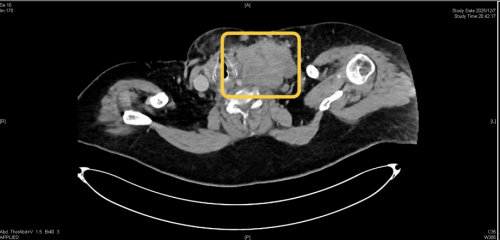

“患者体重达200余斤,1周前无明显诱因逐渐出现活动后呼吸困难,症状持续加重,入院时全身发绀、点头样呼吸、大汗淋漓,脉搏达165次/分(正常为60—100次/分),呼吸达31次/分(正常为12—20次/分),血氧饱和度降低、二氧化碳分压增高,白细胞远高于正常值。”在体格检查时,医生发现患者颈部存在一个较大肿块,CT检查显示,其左颈部至左锁骨上区有一个约10×9cm的巨大包块,气管后方也有一个4.4×4cm的巨大包块,两个包块严重压迫气道、影响呼吸。